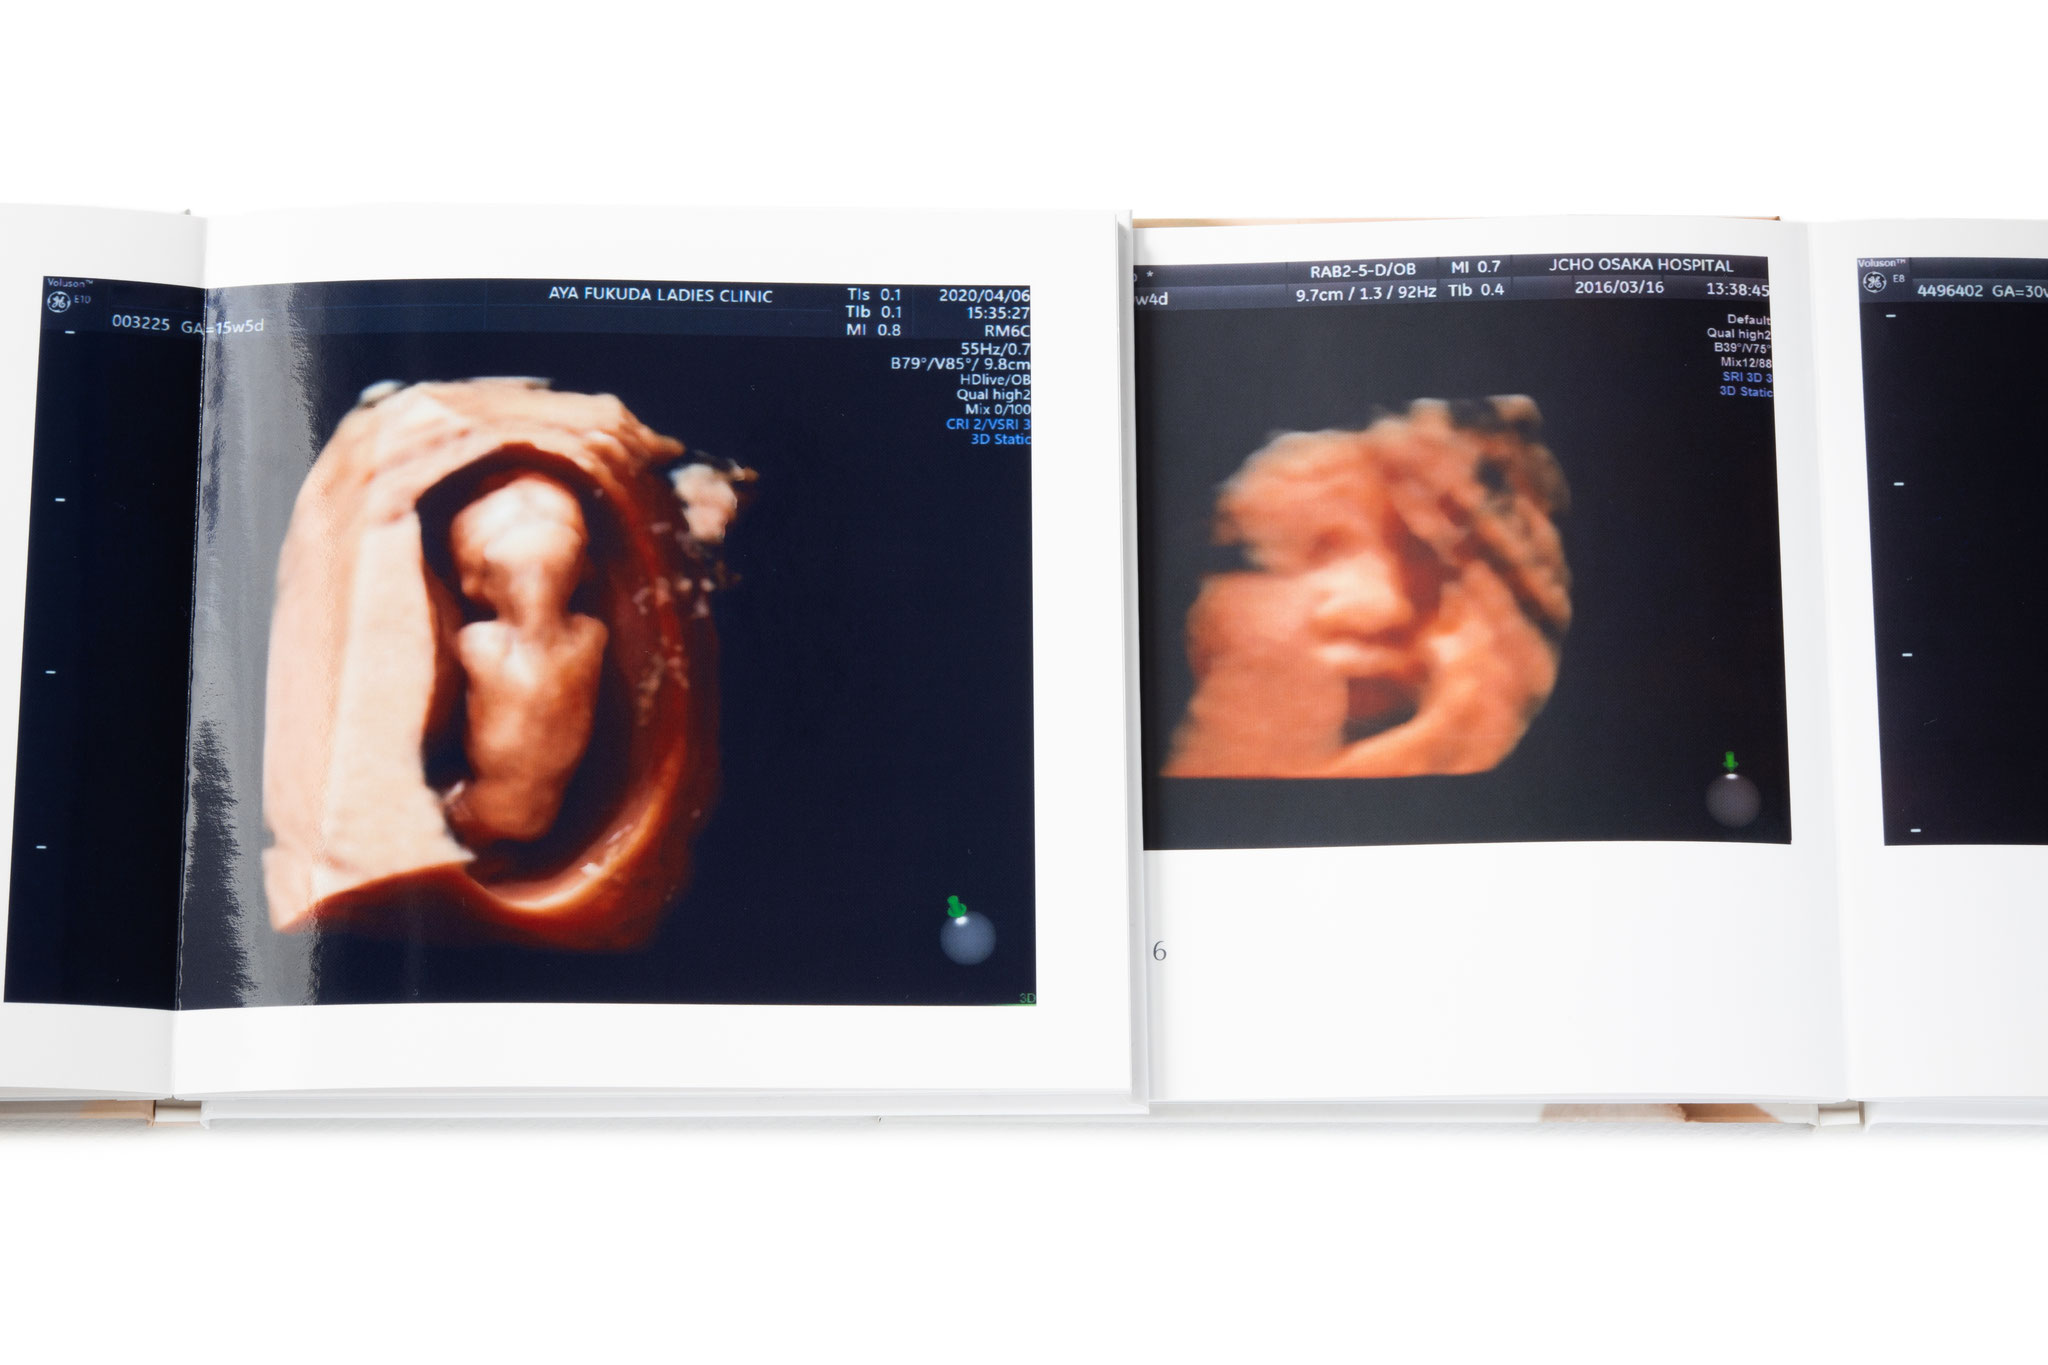

PreBorn BOOK

プレボーンブック

お腹の中の我子を映し出すエコー写真

いつまでも大切にとっておきたいものです

しかし検診でもらう感熱紙のエコー写真は

年月の経過と共に色褪せ消えてしまいます

我子の誕生までの姿を成長記録にして残す

シンプルで高品質のプレボーンブック

サイズ:186 × 186 mm

25,000円(税込27,500円)